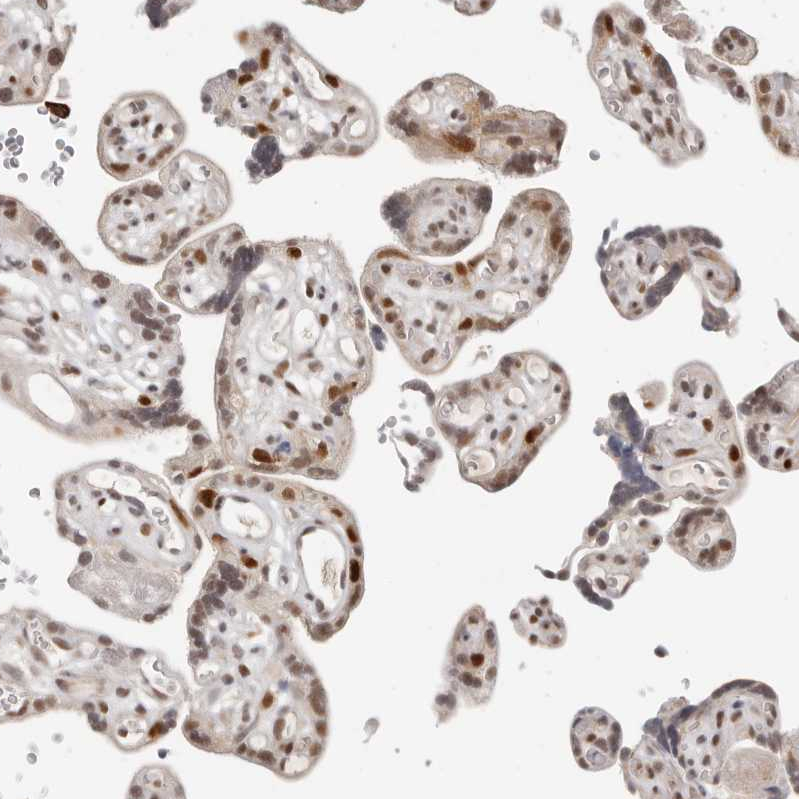

Immunohistochemical staining of human tonsil shows moderate nuclear positivity in germinal center cells.